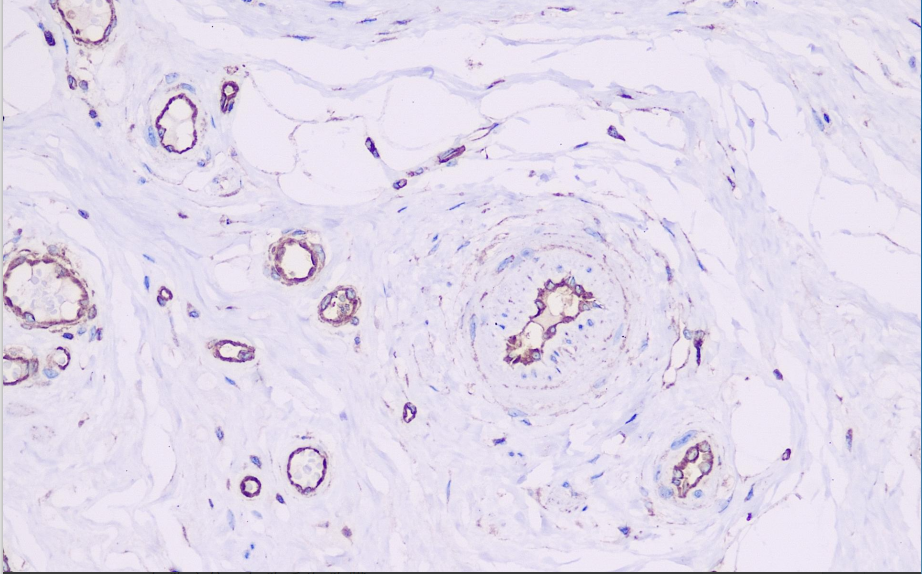

VEGFR2 is highly expressed on tumor vascular endothelial cells, and its binding to vascular endothelial growth factor promotes endothelial cell proliferation, migration and angiogenesis. Tumor angiogenesis can be understood by immunohistochemical detection of VEGFR2. VEGFR2 is an important target for vascular-targeted therapy of tumors, and its expression status can predict the efficacy of anti-angiogenic targeted drugs. For example, in colorectal cancer, if VEGFR2 is highly expressed in tumor tissues, the use of targeted drugs against VEGFR2 such as bevacizumab may be more effective, providing a basis for the clinical selection of appropriate treatment options.

VEGFR2 antibody reagents can specifically bind to the VEGFR2 molecular antigen. Immunohistochemistry kits containing VEGFR2 antibody reagents are suitable for assessing tumor angiogenesis (such as colorectal cancer and renal cancer) and predicting the efficacy of anti-vascular targeted therapies (such as apatinib and ramucirumab).